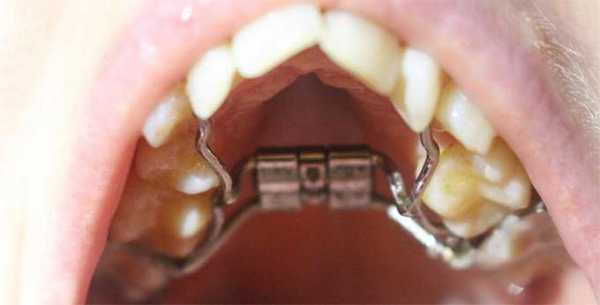

Конструкция аппарата Дерихсвайлера

- Основа - пластина изготовлена из металла или пластмассы. Если остановиться на выборе материала, то металл - это достаточно жёсткий материал, поэтому может вызвать определённый дискомфорт. Однако применение металлических конструкций значительно сокращает сроки лечения. Если говорить о пластмассовых аппаратах - удобны при использовании, но неспособны обеспечить должное давление, благодаря чему сроки исправления дефектов увеличиваются в разы. Также существуют комбинированные варианты.

- В середине основы расположен металлический винт, аппарат дерихсвайлера подкручивать придётся самостоятельно, чтоб увеличить площадь пластины (принцип работы системы рассмотрим ниже).

- По краям основа имеет кольца-крючки (своеобразные дуги фиксаторы), изготовленные из металла в 1-1,2 мм. Эти фиксаторы крепятся к молярам или премолярам. В зависимости от вида патологии могут крепиться и на клыки.

- Как дополнительные элементы конструкция может иметь разнообразные пружинки и винты. Их задача поспособствовать удалению или предотвращению образования щелей между зубами. Иногда в процессе расширения нёба, такой эффект возникает благодаря смещению зубных единиц.

Аппарат Дерихсвайлера изготовляется индивидуально, с учётом размеров ротовой полости и существующих проблем у пациента.

Аппарат устанавливается так, чтоб его основа была по центру нёба. Фиксация основы производится благодаря кольцам, которые надеваются на опорные зубы. Установленный аппарат создаёт определённое давление на челюстные дуги, постепенно расширяя верхнюю челюсть в поперечном направлении и тем самым делая её шире. Увеличивается нагрузка давления при помощи металлического винта, который находится в основе системы. Пациенту составляется график, когда именно и насколько нужно сделать обороты винта.